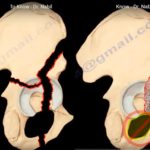

Posterior Column fractures of the Acetabulum

Courtesy: Prof Nabil Ebraheim, University of Toledo, Ohio, USA